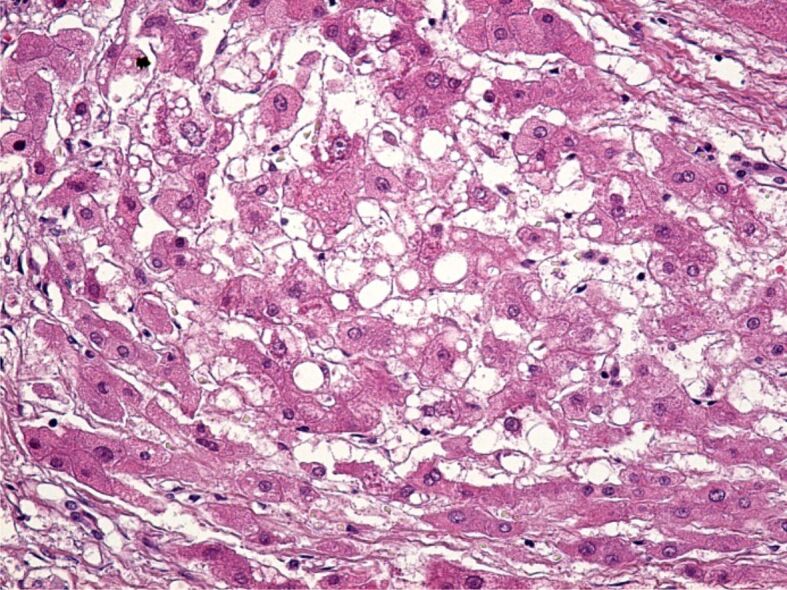

Abstract Image